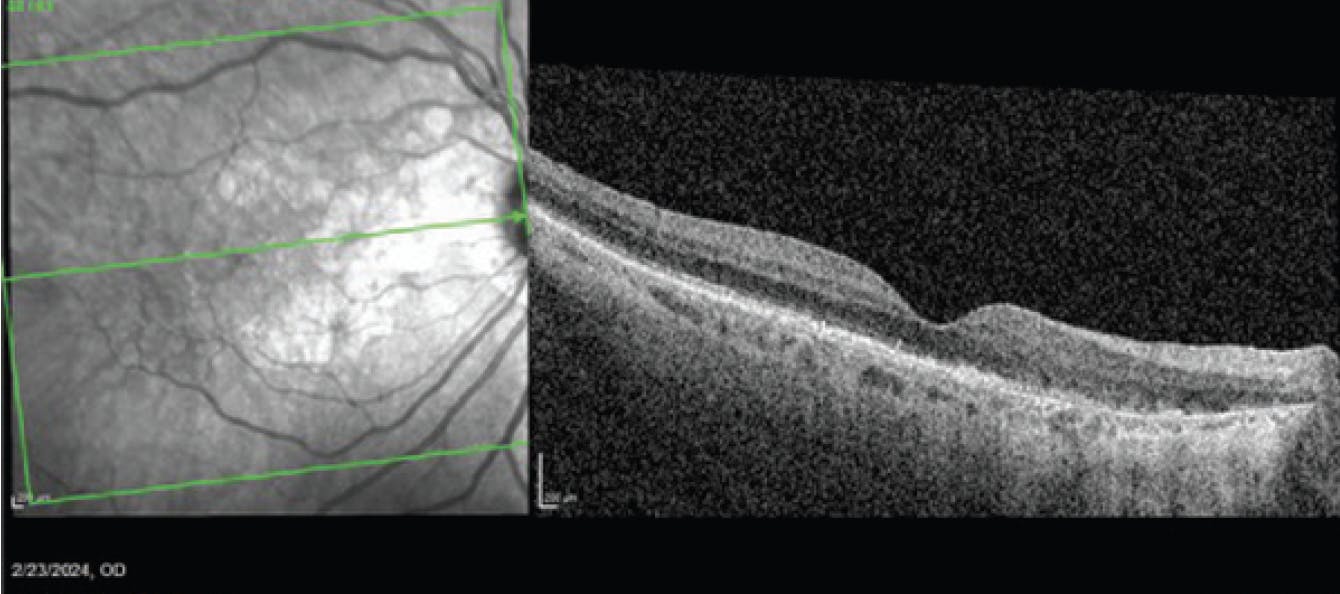

During a January 2024 visit, after 2 monthly injections of avancincaptad pegol, the patient complained of worsening vision OD. On OCT, she was found to have new cystoid macular edema, subretinal fluid, and subretinal hyperreflective material (Figure 4). She was diagnosed with new onset wet AMD and was treated with bevacizumab (Avastin). BCVA at this visit was 20/40. She returned a month later for follow-up, at which time the anatomy had improved, but BCVA was still 20/40 (Figure 5). A second bevacizumab injection was administered.

Figure 5. OCT of the patient in February 2024, 1 month after injection of an anti-VEGF agent to treat the wet AMD.